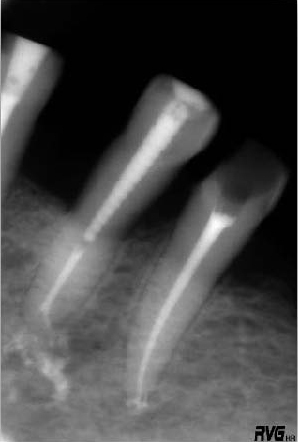

Рассмотрим данную ситуацию на примере обработки канала 35 зуба, который лечили по поводу необратимого пульпита (Рис. 2−4).

Рис.2.

Зуб 35 имел клинические симптомы необратимого пульпита в связи с чем было решено провести его эндодонтическое лечение. Диагностическая рентгенограмма.

Рис. 3.

Зуб был соответствующим образом изолирован. Проведено вскрытие полости пульпы. Канал обработан системой ProFile® до размера .06 20 (series ISO) (а). Рабочая длина контролировалась с помощью апекслокатора (б).

Рис. 4.

Рабочая длина составила 20мм.